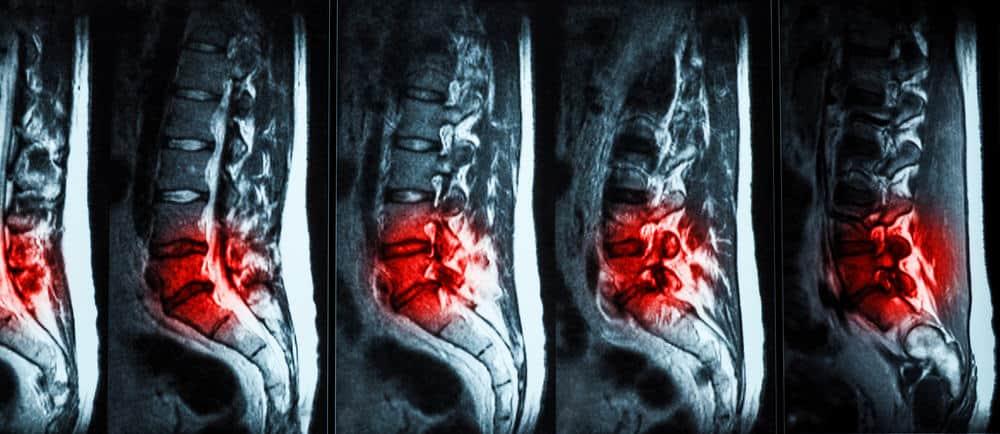

ခါးဆစ်ရိုးကံျွခြင်း (lumar herniated disc ) ကို slipped disc, ဒါမှမဟုတ် prolapsed disc ဆိုပြီး သိထားကြပါတယ်။ ကျောရိုးမကြီးရဲ့ အရိုးနုပြား ကံျွထွက်လာတဲ့အခါ အလယ်က ပျော့ပြောင်းတဲ့နေရာဟာ အက်ကွဲကြောင်းကနေတဆင့် အပြင်အမာနေရာကို ထွက်လာသောအခါ, အနီးအနားက အာရုံကြောတွေအပေါ် ဖိအားသက်ရောက်နိုင်ပြီး နောက်ကျော နာကျင်မှုကိုဖြစ်ပေါ်စေခြင်းသာမက ခြေထောက်တွေ နာကျင်မှုလည်း ရှိနိုင်ပါတယ်။

ခါးဆစ်ရိုးကံျွခြင်း (lumar herniated disc ) ဟာ လူကြီးများမှာ အဖြစ်အများဆုံးကျောရိုးပြဿနာဖြစ်ပါတယ်။